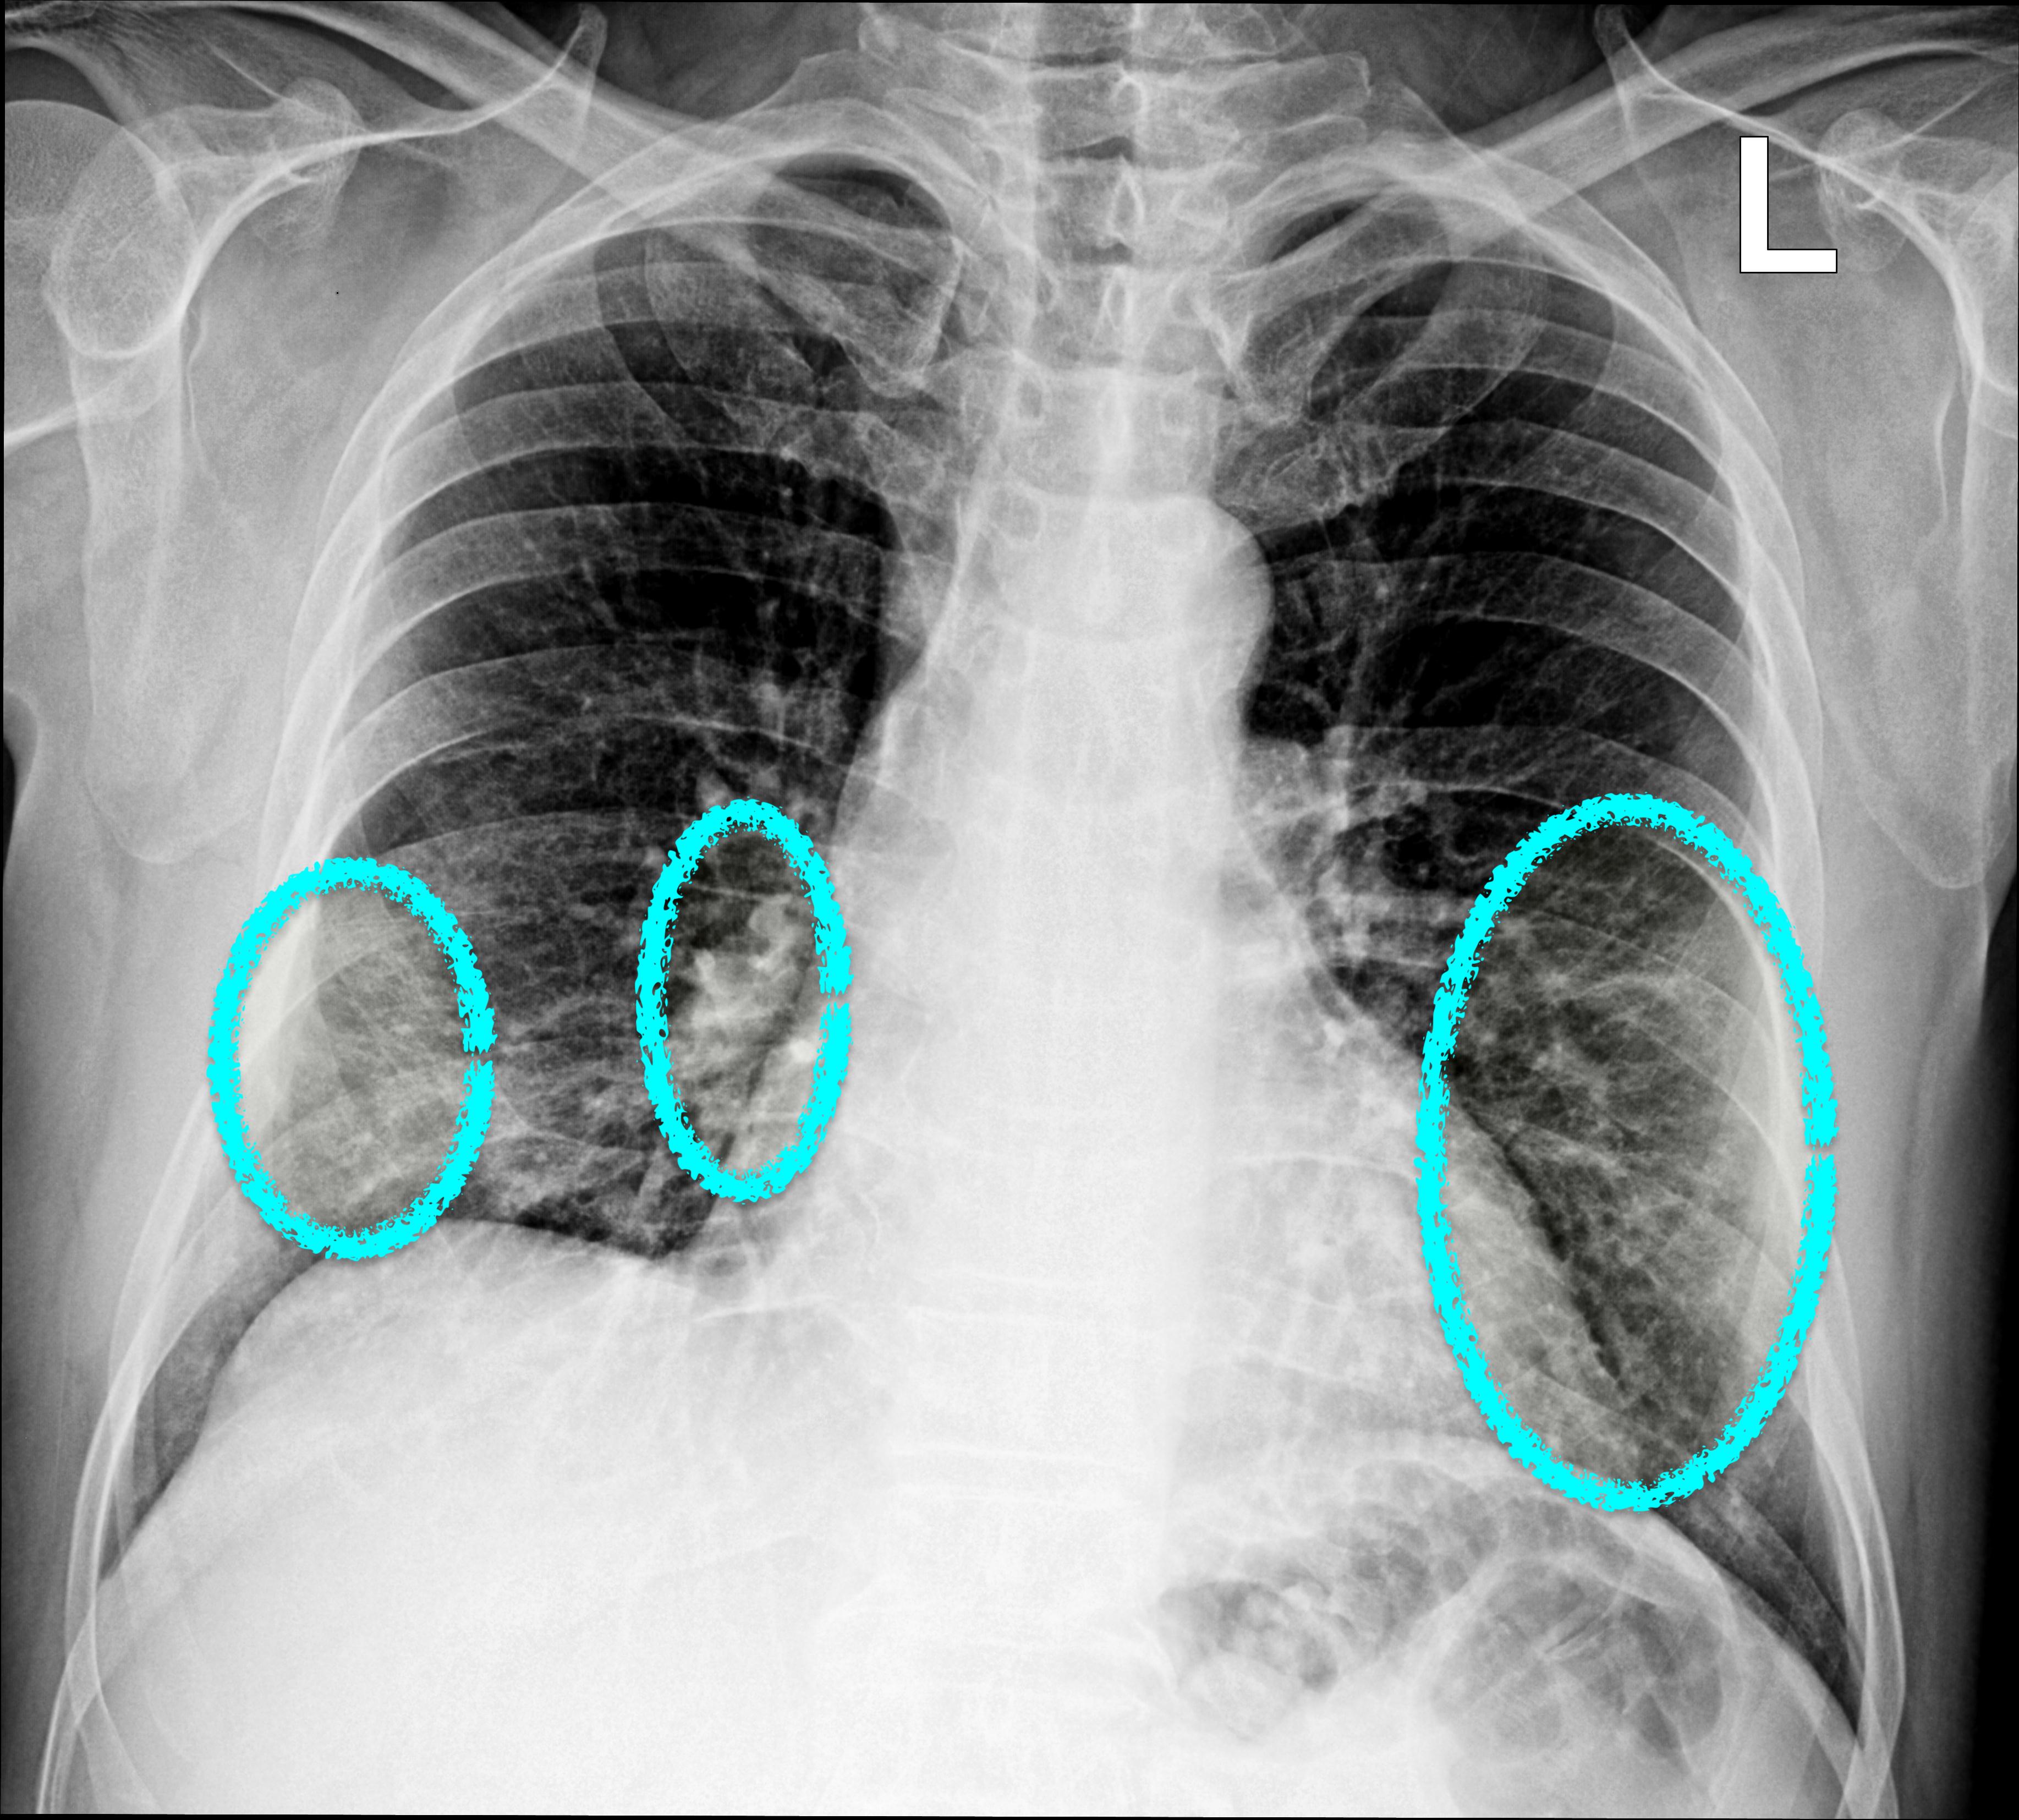

We employ a large-scale of chest X-ray dataset COVIDx [20] to validate the proposed model. It is comprised of 18,543 chest radiography images across 13,725 cases. Example chest X-ray images belonging to normal, pneumonia, and COVID-19 classes from COVIDx dataset are shown in Figure 2. When we examine these examples, we can differentiate these images in terms of features shown within areas marked by the blue circle since we can observe some lighter areas indicating COVID-19 infected regions in the blue circle.